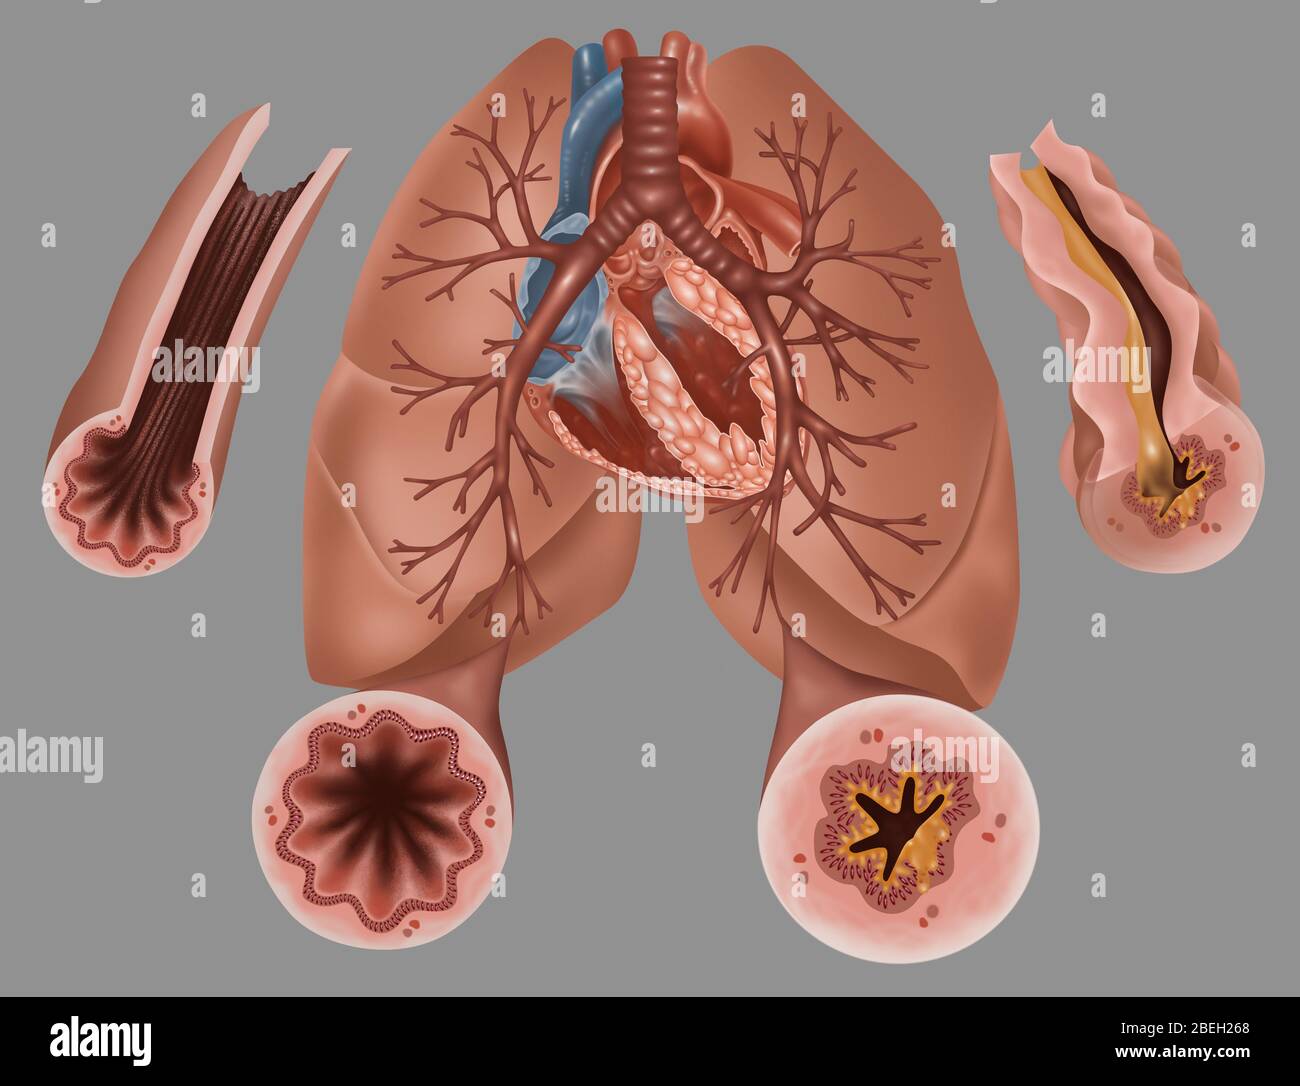

Lungs - Bronchial Mucus. Shown is bronchial airway obstruction and narrowing due to viscid mucus. Stock Photohttps://www.alamy.com/image-license-details/?v=1https://www.alamy.com/stock-photo-lungs-bronchial-mucus-shown-is-bronchial-airway-obstruction-and-narrowing-130806404.html

Lungs - Bronchial Mucus. Shown is bronchial airway obstruction and narrowing due to viscid mucus. Stock Photohttps://www.alamy.com/image-license-details/?v=1https://www.alamy.com/stock-photo-lungs-bronchial-mucus-shown-is-bronchial-airway-obstruction-and-narrowing-130806404.htmlRFHGPMW8–Lungs - Bronchial Mucus. Shown is bronchial airway obstruction and narrowing due to viscid mucus.

Effect of the bronchodilator on a bronchus with an asthma attack (left) and COPD (right). Stock Photohttps://www.alamy.com/image-license-details/?v=1https://www.alamy.com/effect-of-the-bronchodilator-on-a-bronchus-with-an-asthma-attack-left-and-copd-right-image476926507.html

Effect of the bronchodilator on a bronchus with an asthma attack (left) and COPD (right). Stock Photohttps://www.alamy.com/image-license-details/?v=1https://www.alamy.com/effect-of-the-bronchodilator-on-a-bronchus-with-an-asthma-attack-left-and-copd-right-image476926507.htmlRF2JKWTHF–Effect of the bronchodilator on a bronchus with an asthma attack (left) and COPD (right).

COPD (Chronic Obstructive Pulmonary Disease) Stock Vectorhttps://www.alamy.com/image-license-details/?v=1https://www.alamy.com/copd-chronic-obstructive-pulmonary-disease-image236623748.html

COPD (Chronic Obstructive Pulmonary Disease) Stock Vectorhttps://www.alamy.com/image-license-details/?v=1https://www.alamy.com/copd-chronic-obstructive-pulmonary-disease-image236623748.htmlRFRMY404–COPD (Chronic Obstructive Pulmonary Disease)

COPD (Chronic Obstructive Pulmonary Disease) Stock Vectorhttps://www.alamy.com/image-license-details/?v=1https://www.alamy.com/copd-chronic-obstructive-pulmonary-disease-image236623790.html

COPD (Chronic Obstructive Pulmonary Disease) Stock Vectorhttps://www.alamy.com/image-license-details/?v=1https://www.alamy.com/copd-chronic-obstructive-pulmonary-disease-image236623790.htmlRFRMY41J–COPD (Chronic Obstructive Pulmonary Disease)